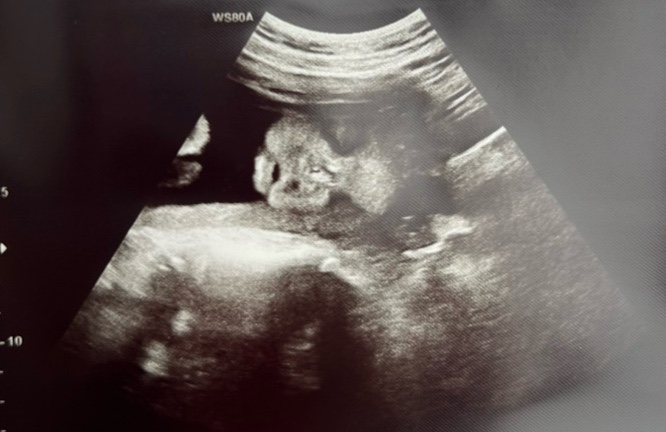

23주 6일 정밀초음파, 독감주사 맞기 그리고 하다 만 임당검사

23주 6일 개월수로는 6개월을 달려가는 날에 정밀초음파와 임신성 당뇨검사가 있었다. 내 생각에 정밀초음...